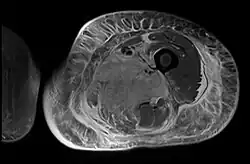

Axial fat suppressed post gadolinium contrast enhancement MRI image showing absent enhancement in the left thigh adductor muscles centrally indicating necrosis in diabetic myonecrosis.